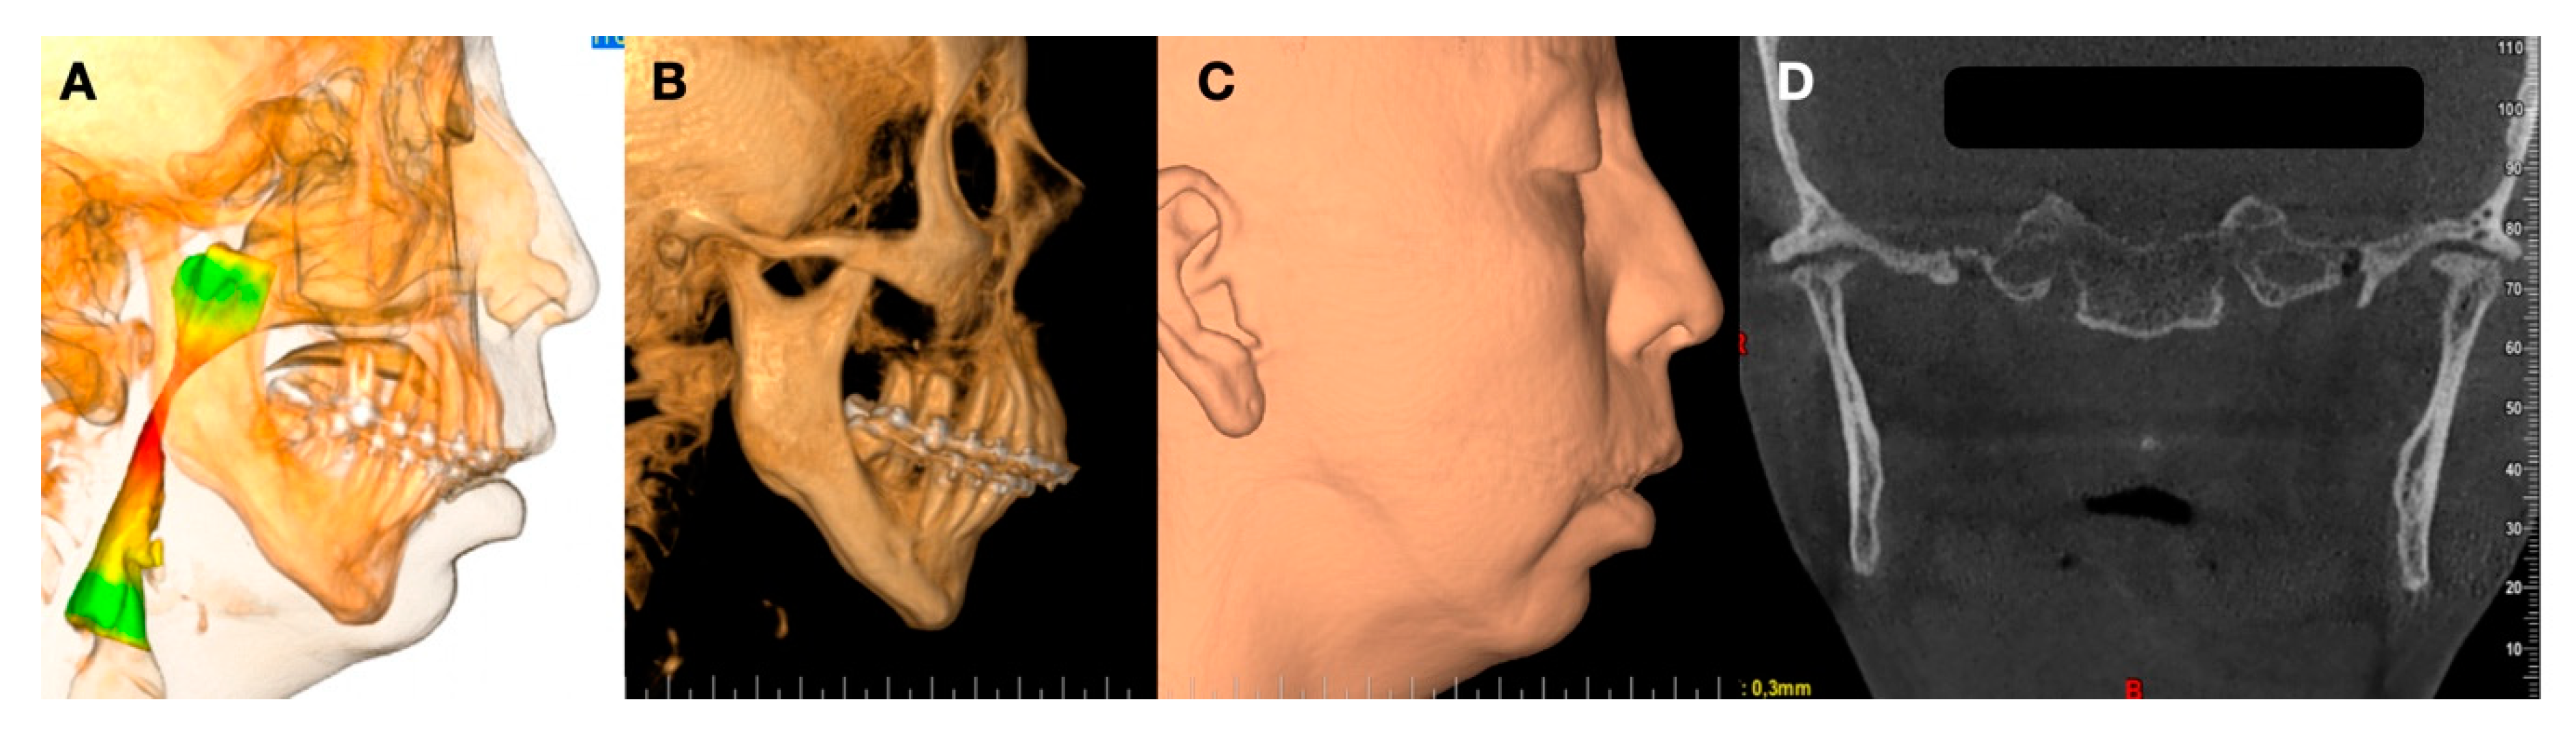

- Volume and Size Reduction of the Mandibular Condyle

- Malformations, Pathology, or Trauma of the Mandibular Condyle